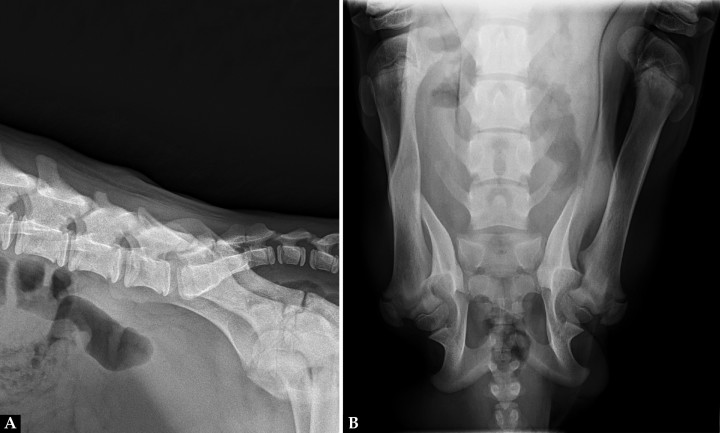

Acudió a consulta una perra mestiza de pastor alemán, entera, de 5 meses de edad y 8,6 kg de peso por paraplejia espástica sin sensibilidad nociceptiva de los miembros posteriores, estirados cranealmente, sin poder adoptar una posición natural en estación y con pérdida de orina por rebosamiento. En su casa de acogida comentaron que había nacido así. Se realizó un estudio radiográfico de la región lumbosacra, con una proyección lateral derecha y otra dorsoventral (Fig. 1).

(A) Radiografía lateral derecha de la región lumbosacra. (B) Radiografía dorsoventral de la región lumbosacra.

En este caso se realizó una radiografía dorsoventral en lugar de una ventrodorsal facilitada por la posición de las extremidades posteriores, rígidas de cadera a tarso y orientadas cranealmente.

En la proyección lateral (Fig. 2A) tanto la apófisis espinosa de la sexta como de la séptima vértebra lumbar tenían una altura reducida. Se observó una disminución de la radiopacidad a nivel de las apófisis articulares entre L6 y L7. El borde cutáneo a nivel de L6 era irregular y el tejido blando subcutáneo presentaba un aumento de su radiopacidad.

En la proyección dorsoventral (Fig. 2B) ambos fémures estaban posicionados en dirección craneolateral a la pared abdominal, los cóndilos rotados medialmente y las rótulas laterales a la diáfisis distal. Sobre el cuerpo y en la línea media de L6 se observaba un área radiolúcida con forma de ojo de cerradura, y no se identificaba la apófisis espinosa. La apófisis espinosa de L7 era corta y redondeada. En la línea media de la primera vértebra sacra se observaba un área radiolúcida y no se visualizaba la cresta medial sagital.